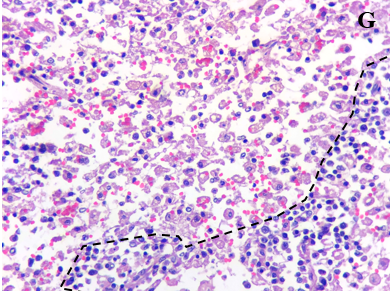

Hình 2. Bệnh tích vi thể của mèo mắc FPV

A) Nang lympho thành ruột tăng sinh (X100); B) Tế bảo biểu mô ruột thoái hóa (X400); C) Viêm phổi kẽ, vách phế nang dày(X200); D) Viêm phế quản, trong lòng phế quản chứa tế bào viêm (X100); E) Lách tăng sinh ở vùng tủy trắng với sự rộng ra của các nang lympho(X10); F) Số lượng tế bào lympho suy giảm mạnh ở vùng tủy trắng và các tế bào tăng sinh chủ yếu là bạch cầu đơn nhân lớn và đại thực bào (X200); G) Số lượng bạch cầu lympho giảm mạnh ở vùng vỏ các nang hạch màng treo ruột (dưới đường đứt nét). Các bạch cầu đơn nhân lớn và đại thực bào tăng mạnh (trên đường đứt nét)